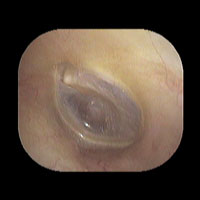

鼓膜は直径約1cm、厚さ約0.1mmの半透明の膜です。正常であれば、鼓膜の奥の空間が透けて見えます。

左急性中耳炎(軽症)

鼓膜がやや赤くなっています。鼓膜の奥に膿が透けて見えています。鼓膜の腫れはありません。抗生剤の内服で鼓膜切開を行わずに7日目で治りました。

初診日